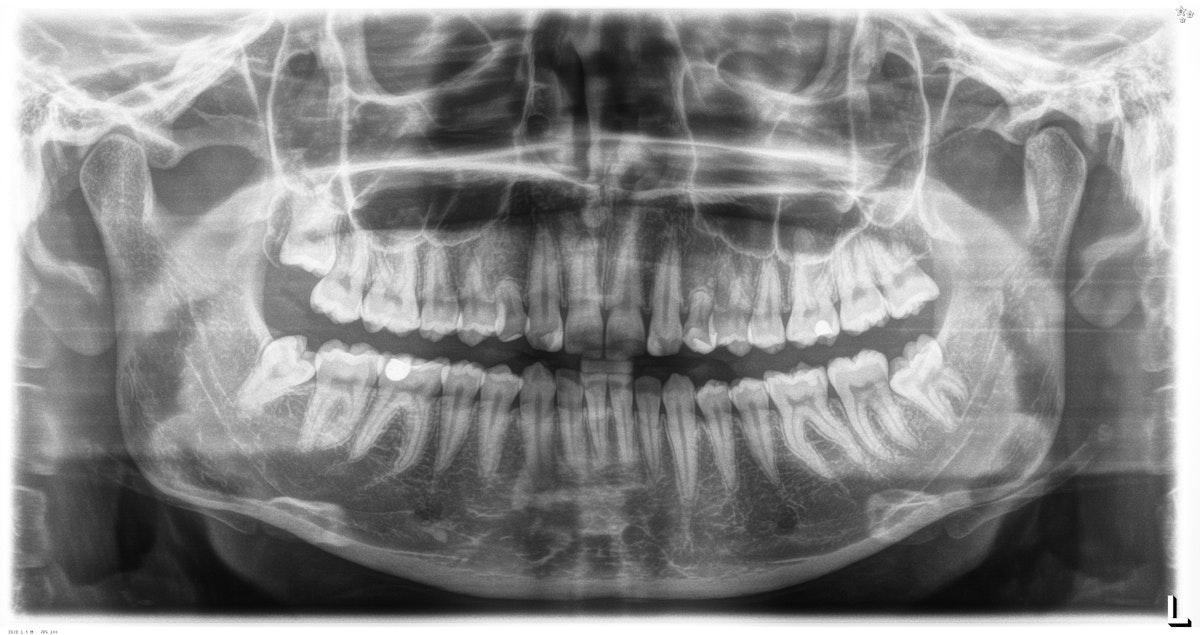

OPTG eli koko leuan rtg kuva alkutilanteesta